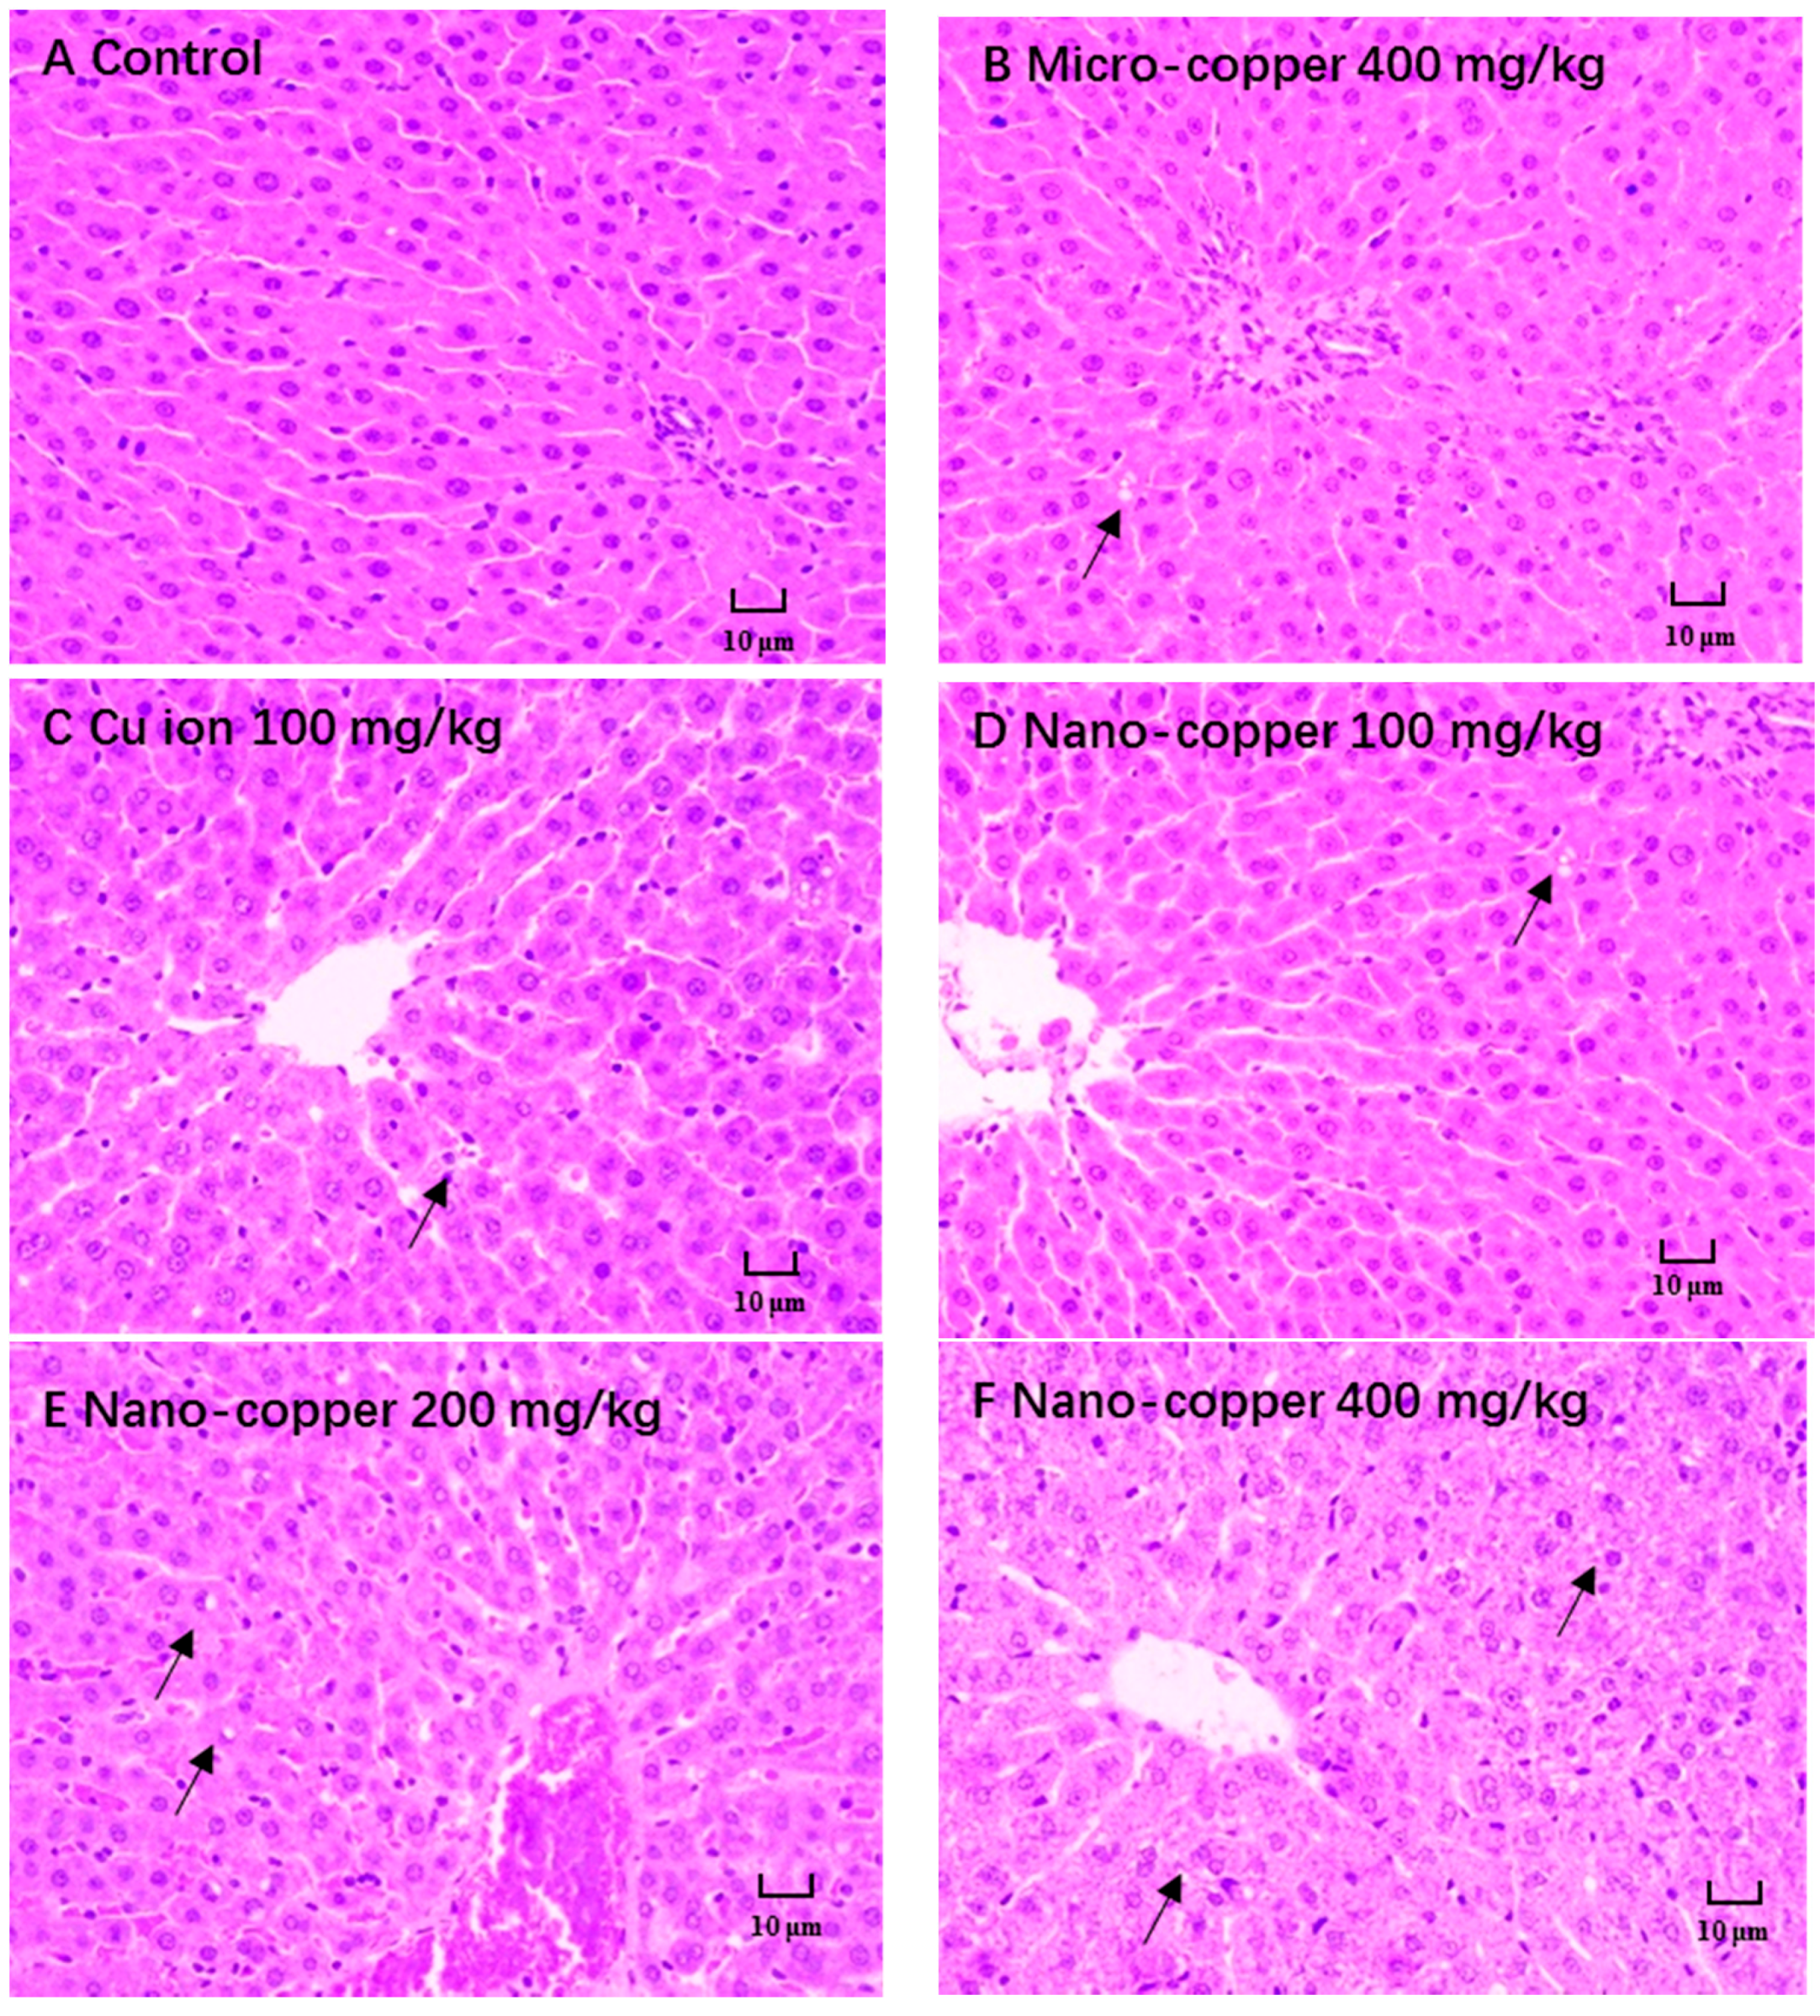

2.2. Histopathological Changes